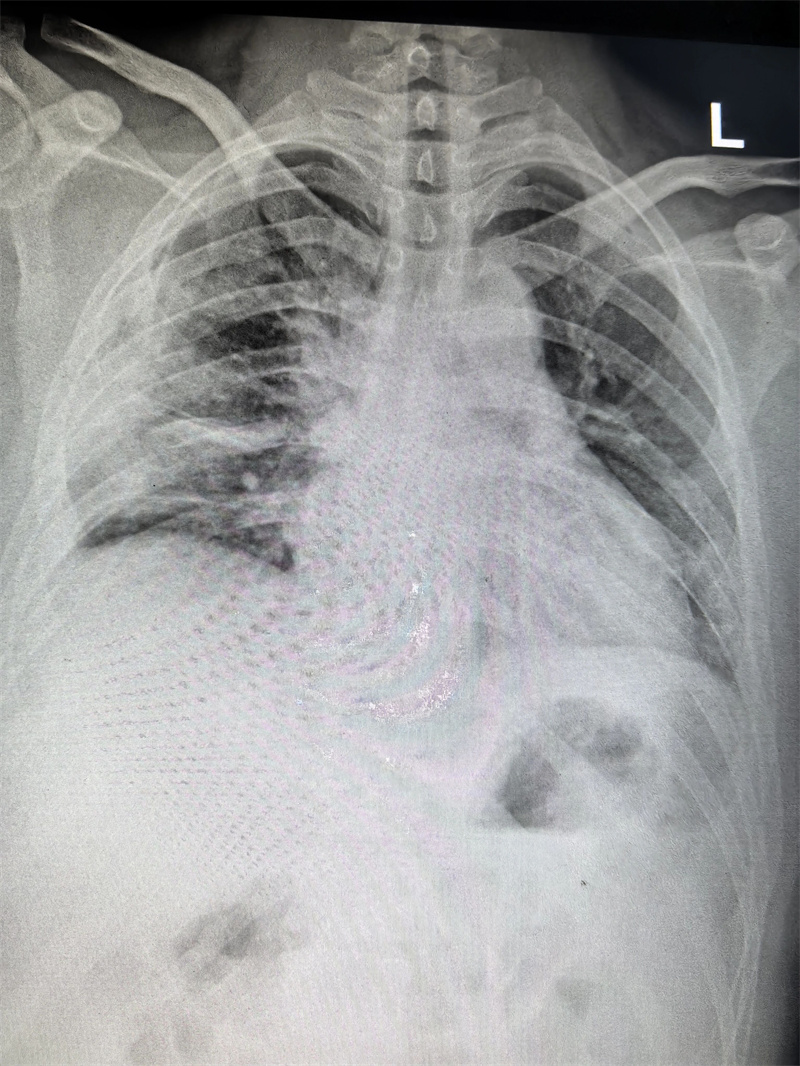

四个月前,23岁的小雨(化名)因胸闷前往医院就诊,CT检查结果显示右侧胸腔靠上位置出现包裹性脓胸,并进行穿刺检查,最终确诊为结核性包裹性脓胸,这个消息让小雨和家人陷入了深深的焦虑之中。

看着日益憔悴的小雨,医生建议手术治疗。术前,田子刚主任和宋巍峰医生在全面评估了小雨各项指标后,确定符合手术标准,便与麻醉科以及护理团队紧密配合,为小雨实施胸腔镜下胸膜剥脱术。

手术室内,胸腔镜在田子刚主任和宋巍峰医生紧密配合操控下,通过小小的切口精准插入小雨体内。在高清显示屏上,胸腔内的情况清晰可见。